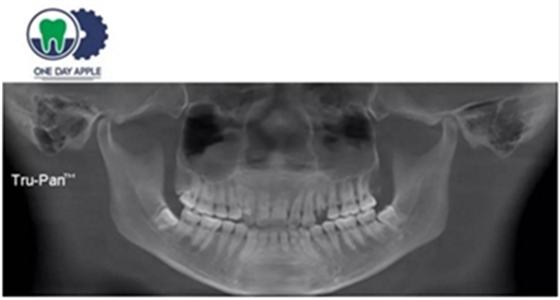

患者、男、40岁,下颌牙缺失数年来院咨询种植。

检查:46缺失, 47倾斜, 1度松动, 未见48萌出,

CBCT:骨量高度及宽度可, 48埋伏,低位阻生.37近中骨吸收

诊断:下颌牙列缺损, 48低位埋伏阻生 37 牙周炎